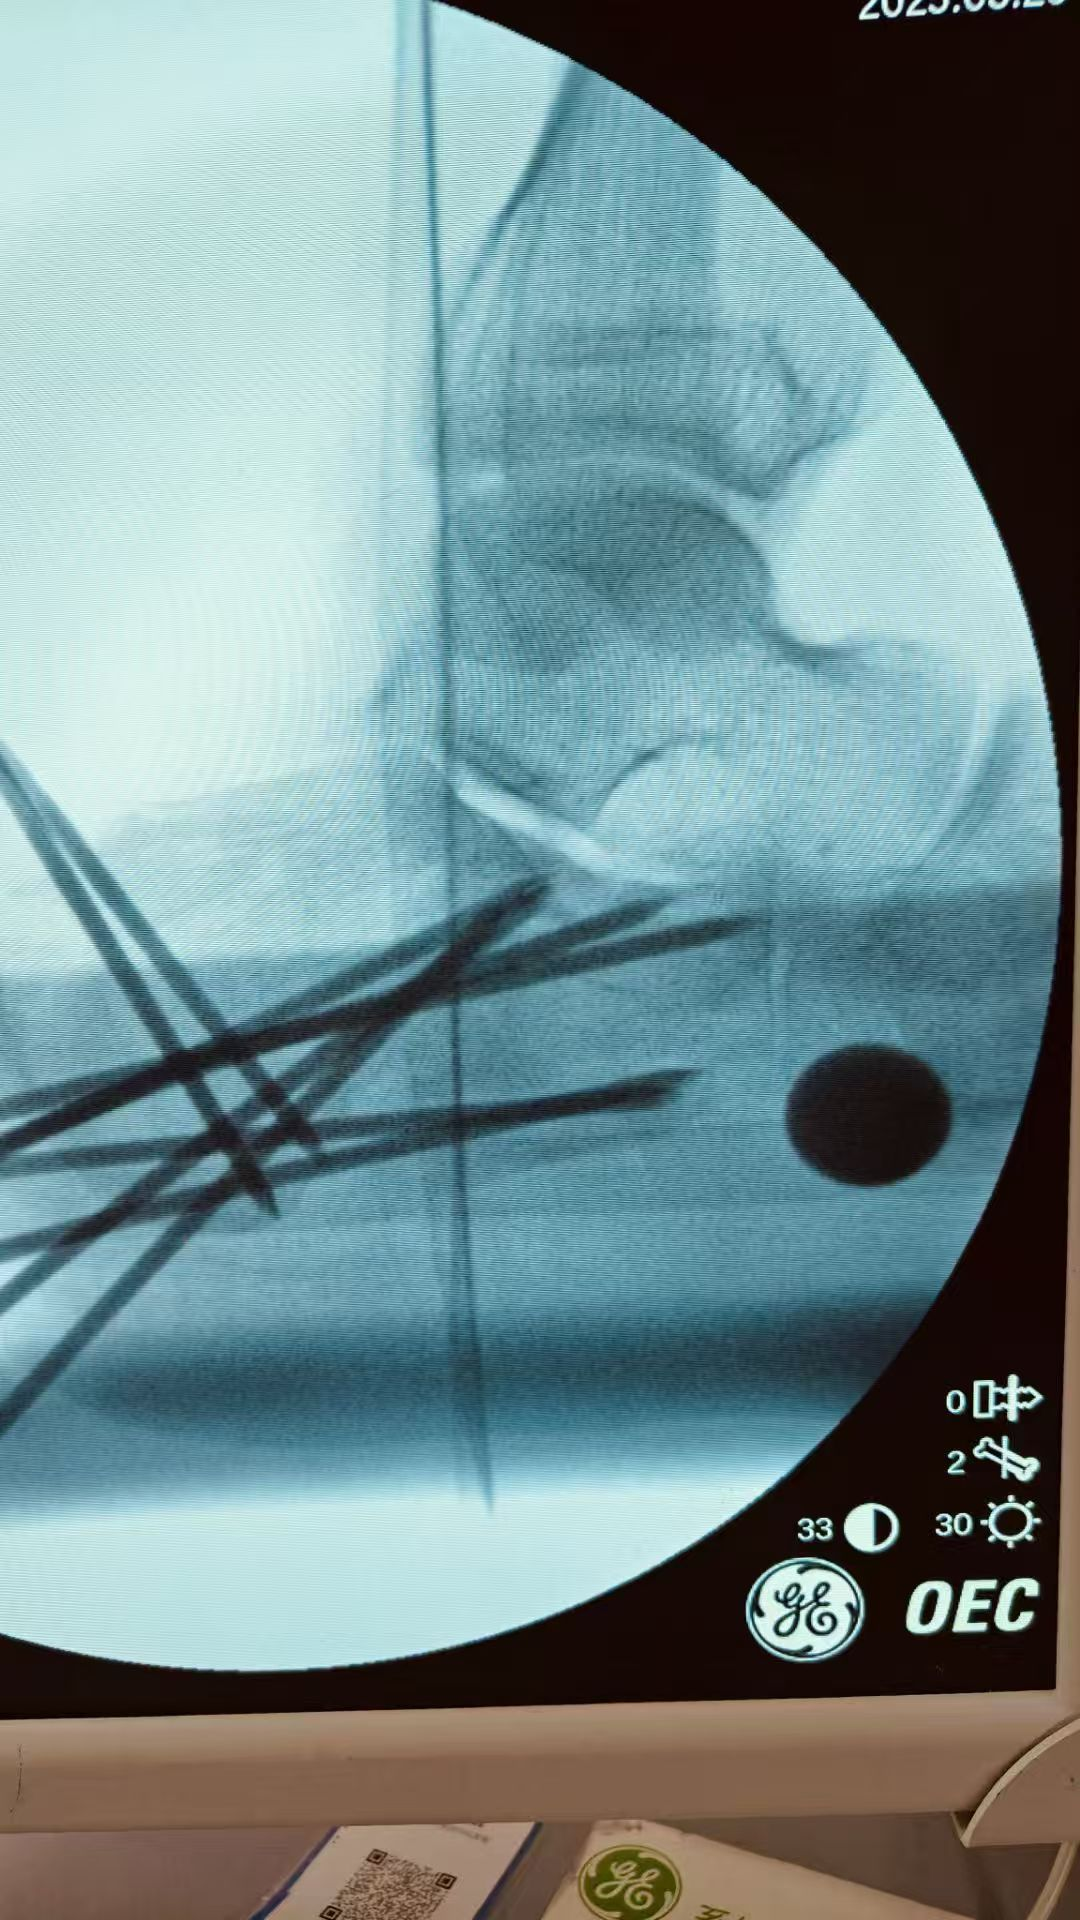

图片图片图片

跟骨粉碎性骨折闭合复位微创经皮穿针内固定